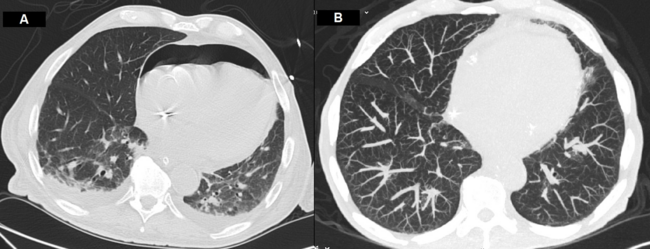

Targeted treatment with fluid challenge, blood transfusion, proton pump inhibitor perfusion, and aminergic support was initiated. While preparing for endoscopy, shock worsened, with arterial systolic pressure dropping to 30-40 mmHg. The echocardiographic evaluation showed a new moderate pericardial effusion. Emergent pericardiocentesis was performed, draining 250 ml of serohematic fluid, which led to clinical improvement. Upper gastrointestinal endoscopy showed abundant clots and active bleeding. Angio-CT scan, aiming at identifying the bleeding vessel for embolization, unexpectedly showed pneumopericardium related to the pericardial drain (Figure 1A), a small pneumothorax, and a moderate pneumoperitoneum. The pericardial drain was removed and conservative treatment was adopted, considering the extremely high operative risk. Good response to treatment ultimately made it possible to discharge the patient home 15 days later, under optimized medical therapy. Subsequently, a month later, he was admitted with symptomatic heart failure and syncopal events. At this point, the possibility of transcatheter aortic valve implantation was considered and the patient was re-evaluated with a CT scan, which showed complete reabsorption of the pneumopericardium (Figure 1B).